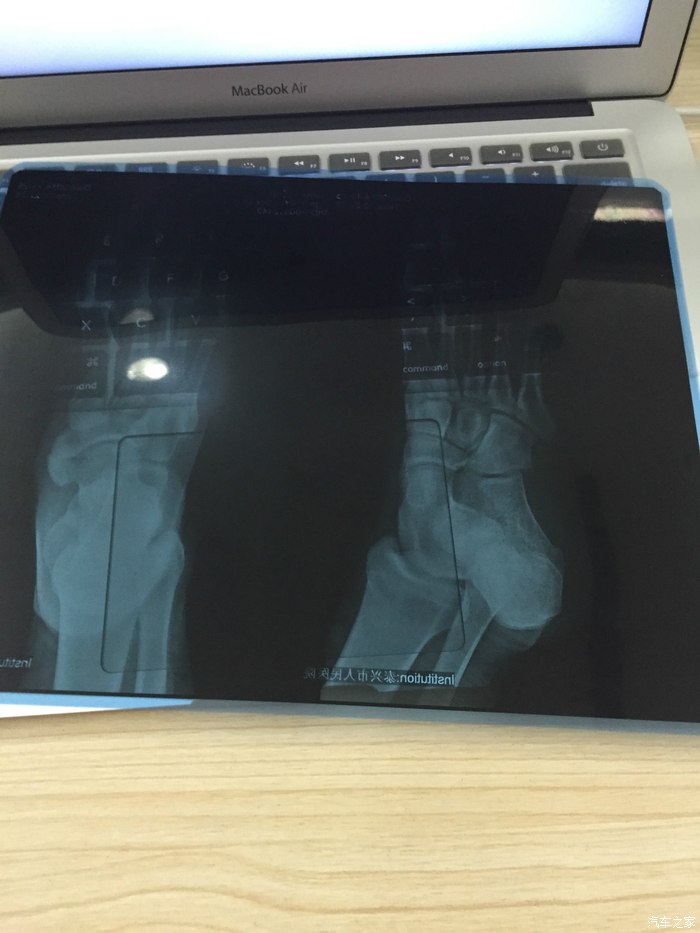

小孩的脑部 ct 检查无恙

小孩的x光片 检查无恙 但是有点肿大